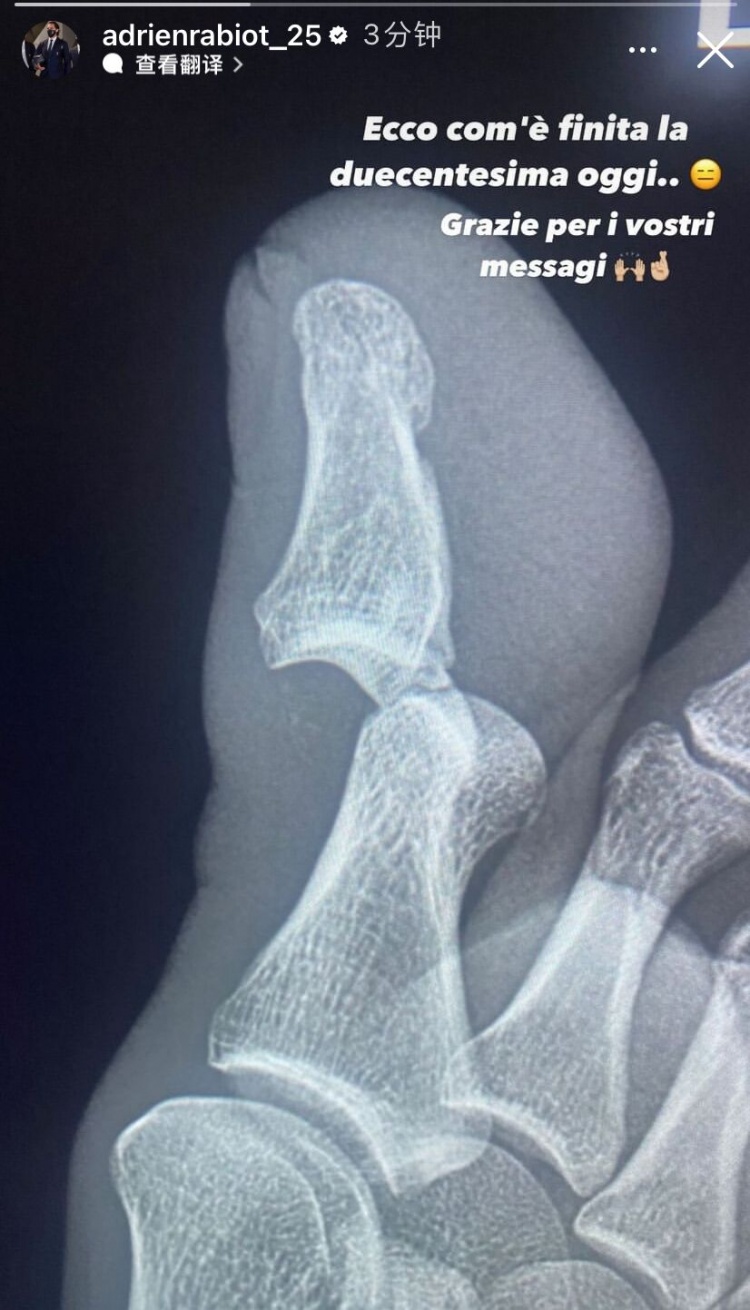

赛后,拉比奥特也发出了自己脚趾的X光图片,可以看出脚趾的确严重脱臼。拉比奥特写道:200场里程碑就这样结束了,感谢大家的暖心留言。